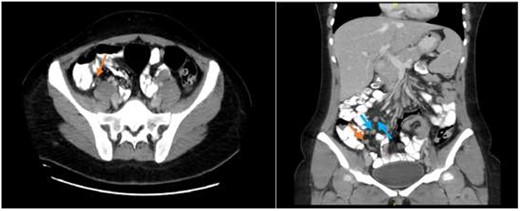

Abdominal CT scan showing an enhanced appendix, not filing with contrast and no surrounding fat stranding or collections (axial view) with associated multiple enlarged inguinal and retroperitoneal lymph nodes (coronal view).

A CT abdomen and pelvis scan was done with oral and intravenous (IV) contrast and displayed features of early uncomplicated appendicitis and multiple enlarged retroperitoneal and inguinal lymph nodes (Fig. 1).